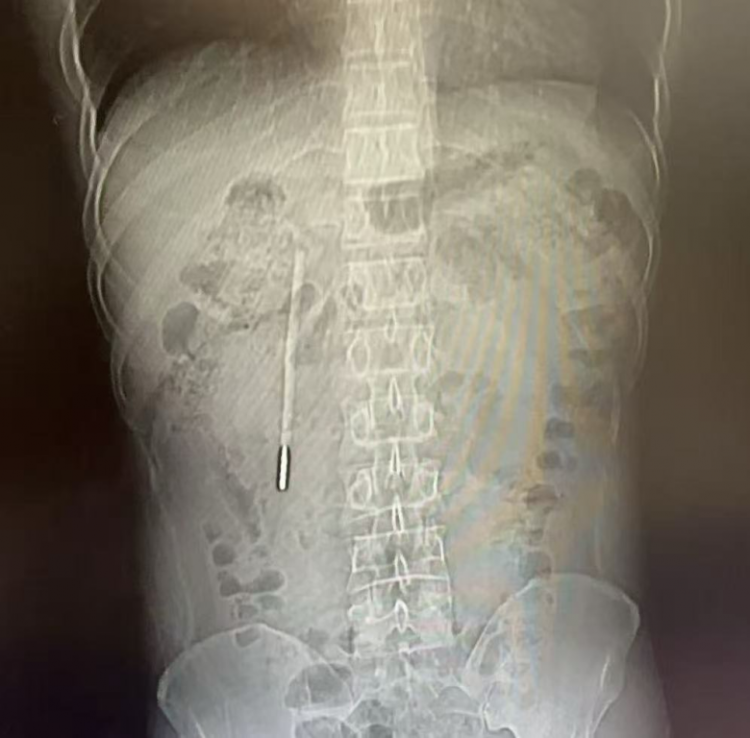

12岁时误吞的一根体温计,竟在肚子里“装璜”了整整20年。近日,温州医科大学附属第一病院医护团队用内镜从患者王先生的十二指肠处取出体温计。

32岁的王先生最近腹部消化不好,赶赴温医大附一院龙港院区就诊。该院区医师对其作念腹部CT查验,发现其十二指肠处有异物,高度怀疑是水银体温计,前端已抵在肠壁上,随时可能激发穿孔、大出血等严重成果。追问病史后得知,这根体温计是王先生12岁时失慎误吞的,其时因发怵不敢见告家长,其家长忙于使命疏于保管,而王先生的体魄也没出现异样,也就没把此事放在心上。

该院内镜中心医护团队立即开展内镜下取物操作。由于体温计淹留时分长、位置深,kaiyun sports且毗邻胆管胰管,操作空间短促,稍有失慎便会毁伤肠壁。团队在相应器械的赞成下精确定位,用圈套器套住体温计一端,缓缓温暖提拉,仅用20分钟便到手将其完整取出,亚博体育取出的体温计除刻度清除外,外不雅好意思满无损。